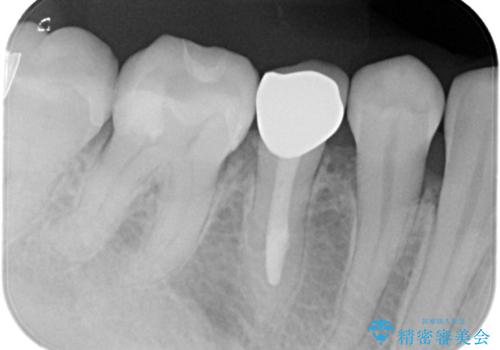

- 笑った時に見える金属を白くしたいとのことでメタルフリーの治療を希望され来院されました。

根管治療を行なったのち、オールセラミッククラウンにて修復処置を行っております。